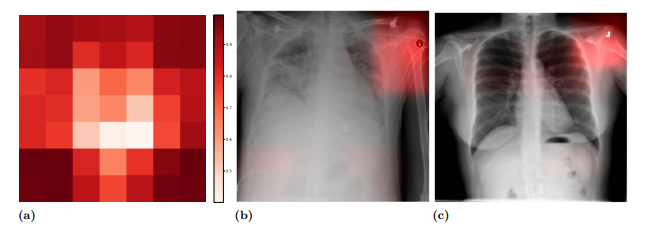

This method led to some concern. Take this example, from this excellent paper by John R. Zech et al. In it, we can see that the model is using a metal token that radiology technicians place on the patient (top right hand corner) during image capture to make the prediction (the token helps Radiologists distinguish left from right later on). The issue is when the model notices that people who have a particular kind of token are also more likely to have some disease, say pneumonia, or cardiomegaly (enlarged heart), the model will seem to use the token when making the prediction.

This project was inspired by the above problem. We know where doctors want the models to look for disease, and we can see where the model is looking, so maybe we can directly teach the model to look in the right place, and show that this helps the model generalize to new situations better.